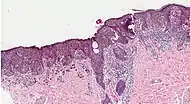

Biopsy

Following a visual examination and a dermatoscopic exam,[75] or in vivo diagnostic tools such as a confocal microscope, the doctor may biopsy the suspicious mole. A skin biopsy performed under local anesthesia is often required to assist in making or confirming the diagnosis and in defining severity. Elliptical excisional biopsies may remove the tumor, followed by histological analysis and Breslow scoring. Incisional biopsies such as punch biopsies are usually contraindicated in suspected melanomas, because of the possibility of sampling error[76] or local implantation causing misestimation of tumour thickness.[77][78] However, fears that such biopsies may increase the risk of metastatic disease seem unfounded.[79][80]

If a lymph node is positive, depending on the extent of lymph node spread, a radical lymph node dissection will often be performed. If the disease is completely resected, the patient will be considered for adjuvant therapy. Excisional skin biopsy is the management of choice. Here, the suspect lesion is totally removed with an adequate (but minimal, usually 1 or 2 mm) ellipse of surrounding skin and tissue.[117] To avoid disruption of the local lymphatic drainage, the preferred surgical margin for the initial biopsy should be narrow (1 mm). The biopsy should include the epidermal, dermal, and subcutaneous layers of the skin. This enables the histopathologist to determine the thickness of the melanoma by microscopic examination. This is described by Breslow's thickness (measured in millimeters). However, for large lesions, such as suspected lentigo maligna, or for lesions in surgically difficult areas (face, toes, fingers, eyelids), a small punch biopsy in representative areas will give adequate information and will not disrupt the final staging or depth determination. In no circumstances should the initial biopsy include the final surgical margin (0.5 cm, 1.0 cm, or 2 cm), as a misdiagnosis can result in excessive scarring and morbidity from the procedure. A large initial excision will disrupt the local lymphatic drainage and can affect further lymphangiogram-directed lymphnode dissection. A small punch biopsy can be used at any time where for logistical and personal reasons a patient refuses more invasive excisional biopsy. Small punch biopsies are minimally invasive and heal quickly, usually without noticeable scarring.